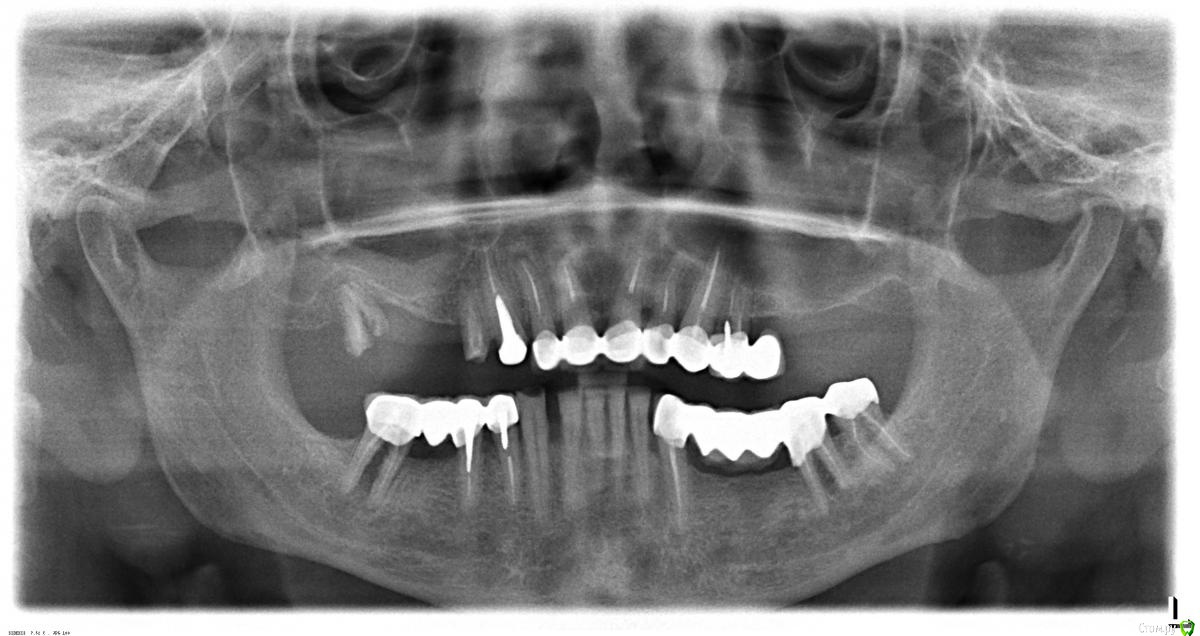

pit Опубликовано 6 мая, 2016 Поделиться Опубликовано 6 мая, 2016 поставить в синус имплант или нет будет видно на кт или по факту. но скорее нет чем да. остальное как вы обозначилиЯ поделюсь своим опытом С 2003 по 2008 я оперировал по ОПТГ, боковомку снимку черепа и снимку черепа в полуаксиальной проекции. Лишь в крайних случаях прибегал к спиральной КТ. С 2008 г повсеместно в СПб появилась КЛКТ и наступило счастье)). В 2011-2012гг мне пришлось работать по ОПТГ в другом городе и, честно говоря, было сначала не по себе. А потом все стало на свои места. Ведь основная проблема- невозможность оценить толщину на в/челюсти. Но в боковом отделе это не такая уж проблема.В данном случае есть пристеночное утолщение слизистой, не определяются септы в лунках 14 и 17 зубов корни(т е ширина достаточная). Что касается анастомоза - при препарировании его хорошо видно, повредить его Вы можете как зная о нем, так и не зная. Проблема будет при диаметре сосуда более 2 мм но это редко бывает.Единственная теоритичеки возможная проблема- септа в сагитальном направлении, об этом следует помнить.По ОПТГ размеры имплантов 14з - 4,3х13, 15з- 3,5х10, 17з- 5,0х10. Ну и, конечно же, близкие типоразмеры должны быть в клинике во время операции. 1 Ссылка на комментарий